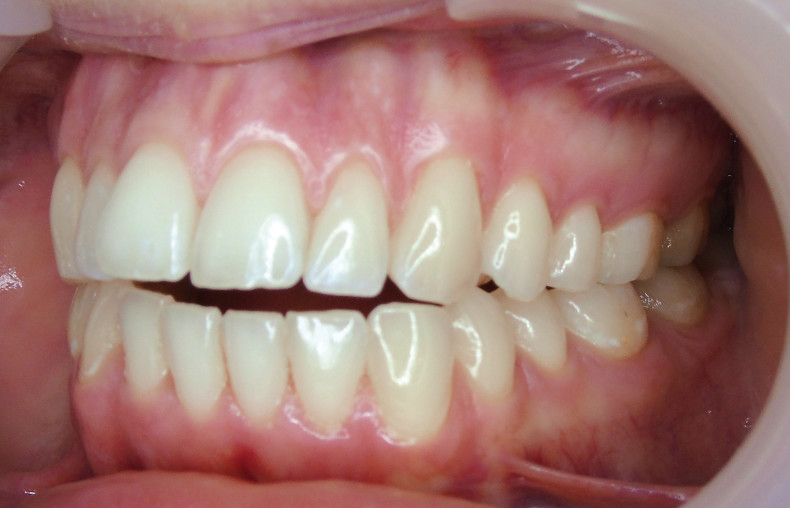

Sechs Monate nach Abschluss der Therapie besteht weiterhin ein stabiles Ergebnis. Wie im Vergleichsbild (Abb. 5a–c) zu sehen ist, konnte die geplante vertikale Korrektur vollständig erzielt und die Mittellinie bis auf eine MLV von 1 mm nach rechts im UK korrigiert werden.

Somit kann gezeigt werden, dass auch ohne operativen Eingriff oder festsitzende Apparaturen in kürzester Zeit ein ästhetisch und funktionell zufriedenstellendes Ergebnis erzielt werden kann (Abb. 6a–c; Abb. 7a–e). Es wird daher nachvollziehbar dargestellt, dass bei entsprechender Indikation Aligner für die Behandlung frontal offener Bisse eine hervorragende Alternative zu den konventionellen Behandlungsmethoden sein können. Voraussetzung für diesen Therapieansatz ist ein motivierter Patient mit guter Compliance.